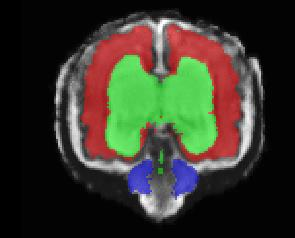

Limiting failures of machine learning systems is of paramount importance for safety-critical applications. In order to improve the robustness of machine learning systems, Distributionally Robust Optimization (DRO) has been proposed as a generalization of Empirical Risk Minimization (ERM). However, its use in deep learning has been severely restricted due to the relative inefficiency of the optimizers available for DRO in comparison to the wide-spread variants of Stochastic Gradient Descent (SGD) optimizers for ERM. We propose SGD with hardness weighted sampling, a principled and efficient optimization method for DRO in machine learning that is particularly suited in the context of deep learning. Similar to a hard example mining strategy in practice, the proposed algorithm is straightforward to implement and computationally as efficient as SGD-based optimizers used for deep learning, requiring minimal overhead computation. In contrast to typical ad hoc hard mining approaches, we prove the convergence of our DRO algorithm for over-parameterized deep learning networks with ReLU activation and a finite number of layers and parameters. Our experiments on fetal brain 3D MRI segmentation and brain tumor segmentation in MRI demonstrate the feasibility and the usefulness of our approach. Using our hardness weighted sampling for training a state-of-the-art deep learning pipeline leads to improved robustness to anatomical variabilities in automatic fetal brain 3D MRI segmentation using deep learning and to improved robustness to the image protocol variations in brain tumor segmentation. Our code is available at https://github.com/LucasFidon/HardnessWeightedSampler.